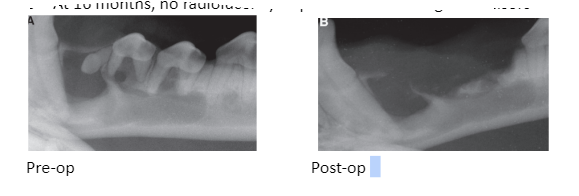

JVD 2014, Honzelka, Modified Conservative Treatment of an Extensive Dentigerous Cyst in a Dog, which of the following is true?

a) DTC originates from the remaining enamel organ or reduced enamel epithelium that surrounds the crown during odontogenesis

and attaches to the tooth at the cementoenamel junction

JVD 2014, Honzelka, Modified Conservative Treatment of an Extensive Dentigerous Cyst in a Dog, which of the following treatment options was pursued?

c) Subtotal cystic lining debridement and extraction